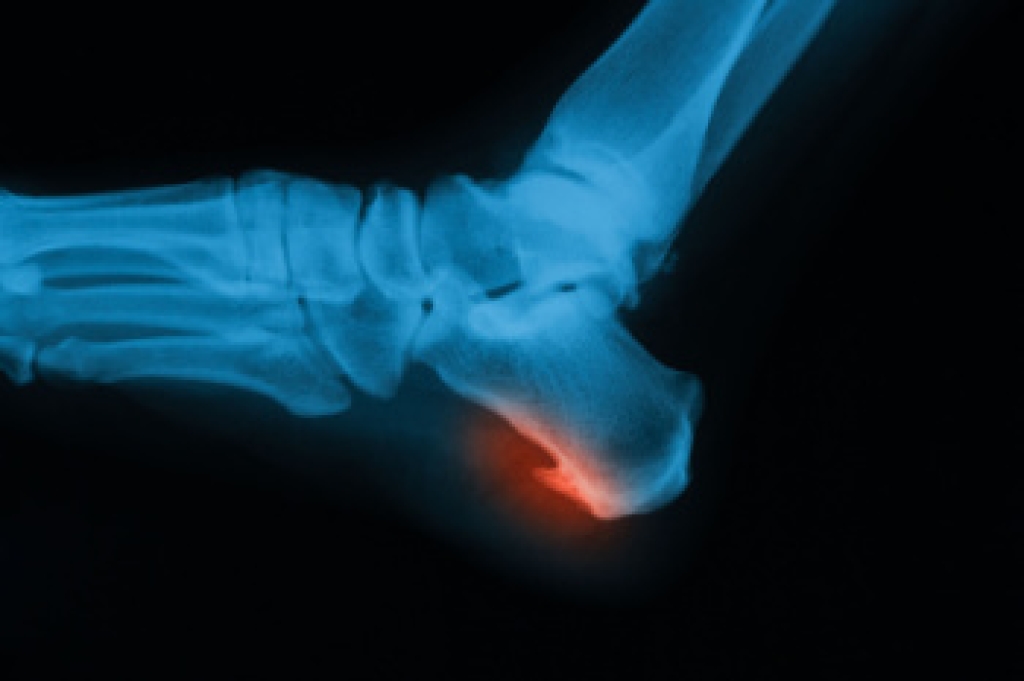

Due to the wide variety of potential causes of ankle pain, podiatrists will utilize a number of different methods to properly diagnose ankle pain. This can include asking for personal and family medical histories and of any recent injuries. Further diagnosis may include sensation tests, a physical examination, and potentially x-rays or other imaging tests.

To figure out the cause of foot pain, podiatrists utilize several different methods. This can range from simple visual inspections and sensation tests to X-rays and MRI scans. Prior medical history, family medical history, and any recent physical traumatic events will all be taken into consideration for a proper diagnosis.